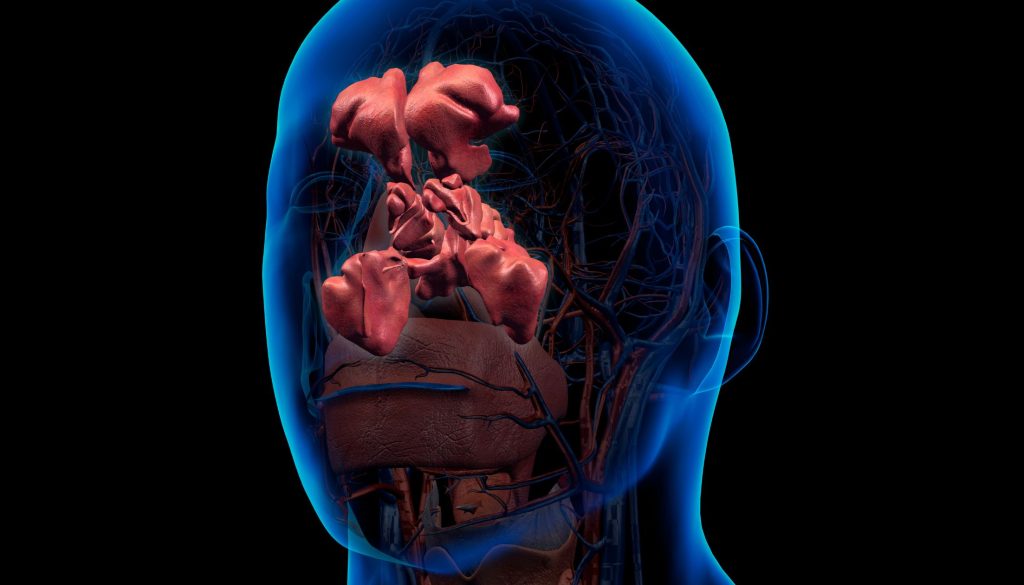

أولاً: مقدمة عن أمراض الأنف والأذن والحنجرة

تشمل تخصصات الأنف والأذن والحنجرة مجموعة واسعة من الحالات المرضية التي تؤثر على هذه الأعضاء الحيوية. تتضمن بعض الأمراض الشائعة في هذا المجال:

1. **التهابات الأنف والجيوب الأنفية**: نزلات البرد، التهاب الجيوب الأنفية المزمن.

2. **مشاكل السمع**: انخفاض السمع، طنين الأذن، انسداد الأذن.

3. **خلل أو مشاكل في الحلق**: التهاب اللوزتين، التهابات الحلق، الشخير واضطرابات النوم.